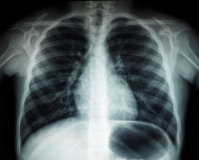

Nguyên nhân các vị trí trên phim chụp X-quang có độ đậm, nhạt khác nhau là

Nguyên nhân các vị trí trên phim chụp X-quang có độ đậm, nhạt khác nhau là do